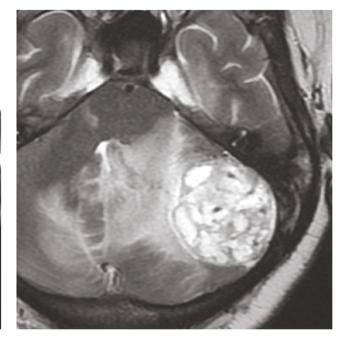

L’image

du jour

Illustration

Cancer de la prostate

Le « Movember » – qui se déroule chaque mois de novembre – a pour but de sensibiliser la population à la lutte contre les cancers masculins, dont le cancer de la prostate qui est en première position (26,5 % des cancers chez les hommes de plus de 65 ans).